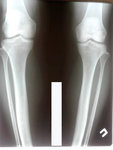

Дата снятия - 02.11.2018г.

Срок сращения - 98 дней.